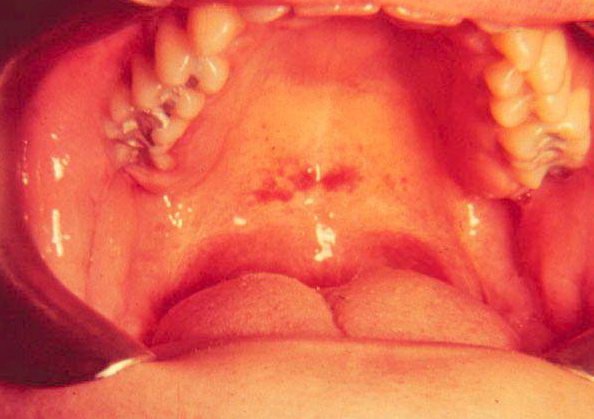

Mononucleosis = داء كثرة وحيدات النوى